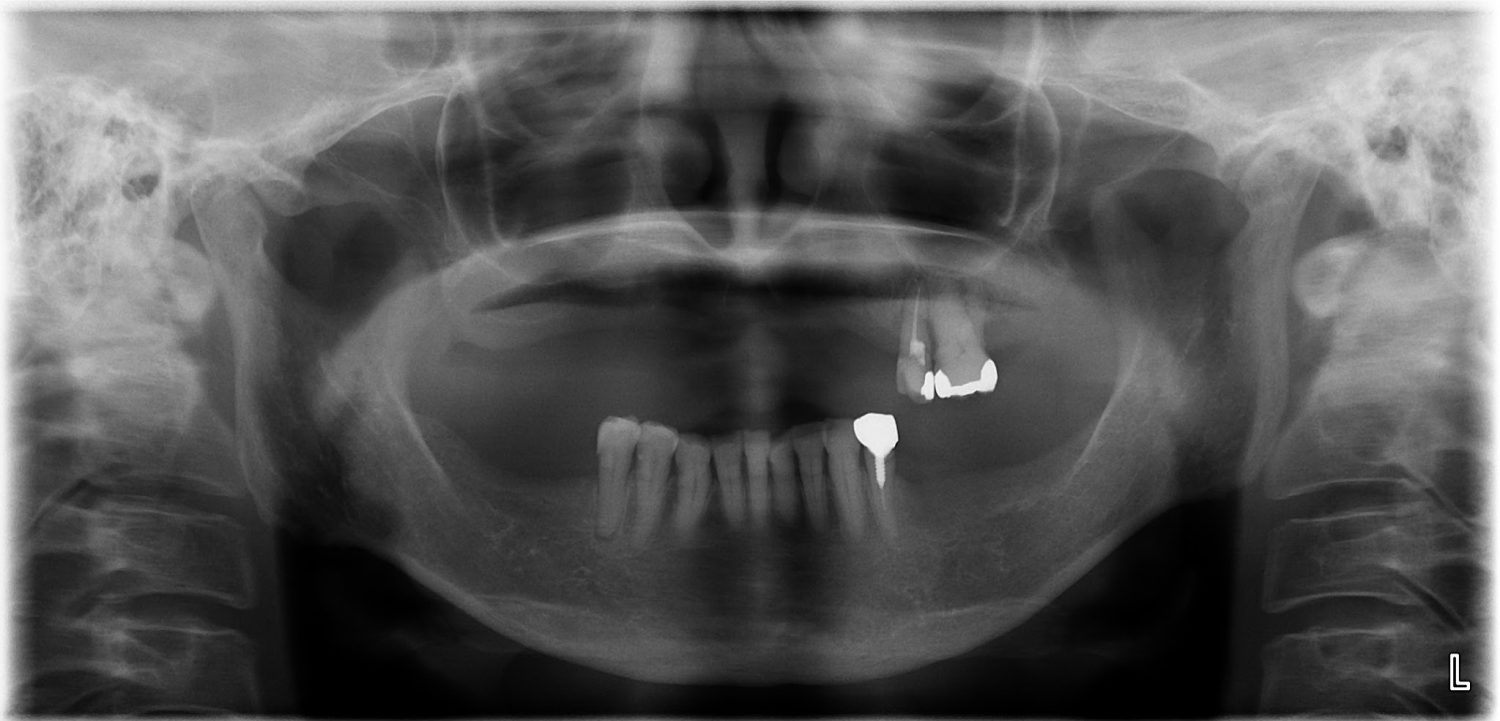

インプラント治療の症例紹介④

Before

After

主訴

義歯による疼痛

治療内容

下顎舌側に骨隆起があり義歯困難な状態。保存不可能な歯の抜歯を行い、インプラントを埋入し咬合再構成を行った。

治療費

2,851,200円(税込)

治療期間

29ヶ月

通院回数

26回

想定されたリスク

※咬合力の強い方なので、予防的にマウスピースの装着が必要。インプラント周囲炎の恐れがありました。

濱 仁隆先生

浜歯科

歯の欠損の対合歯の挺出等を修正し咬合平面を揃え咬合再構成を行った症例。